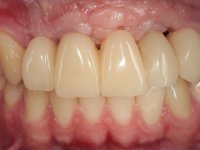

Reabilitação fixa do sector antero-superior após traumatismo resultante de acidente de viação.

Paciente do sexo masculino, com 22 anos de idade e não fumador. Apresentou-se na consulta 6 meses após um acidente de viação em que perdeu os dentes 21, 22, 23 e 24. Os dentes 12 e 11 apresentavam mobilidade grau 3 apresentando-se também com extracção indicada. A arquitectura gengival da zona desdentada apresentava-se retraída e planificada.

O paciente foi observado conjuntamente e a dúvida que surgiu de imediato foi se seria possível com a regeneração óssea a efectuar poder ser reabilitada naturalmente a zona das papilas interdentárias. Nesse sentido foi feito um enceramento de diagnóstico que contemplaria as duas hipóteses, utilizando ou não a cerâmica gengival. A confecção desse enceramento foi fundamental para expor ao paciente a dificuldade da reabilitação. O wax-up deu origem a um mock-up que foi aprovado pelo paciente e que simultaneamente serviu de guia imagiológica. O caso foi planificado cirurgicamente e realizada uma guia cirúrgica com que foram colocados os implantes. Após 10 semanas foi feita a 1ª impressão para confecção da ponte provisória. Foram criados os primeiros perfis de emergência na gengiva artificial e foi digitalizado o modelo. Por processo de CAD-CAM foi confeccionada uma ponte provisória aparafusada baseada no enceramento de diagnóstico. A ponte trabalhou durante 8 semanas os tecidos moles que foram fielmente copiados numa impressão com técnica de moldeira aberta. Os transferes foram individualizados com resina composta para copiarem fielmente os perfis de emergência criados pela ponte provisória. Confeccionado o modelo de trabalho definitivo, foi realizada uma infra-estrutura em zircónio seguindo a orientação do enceramento de diagnóstico. O assentamento da infra-estrutura foi testado em boca e simultaneamente foi novamente impressionados os tecidos moles com um silicone fluido. Nessa consulta foi feito o levantamento da cor. Os dentes 13 e 23 apresentavam uma saturação anormalmente forte que resolvemos não valorizar, optando por privilegiar a relação com o sector antero-inferior. Foi realizada uma nova gengiva artificial com a impressão que acompanhou a impressão de arrasto com a infra-estrutura. Após a colocação da cerâmica na infra-estrutura foram coladas as meso-estruturas. O trabalho final foi aparafusado lentamente permitindo a adaptação dos tecidos moles.